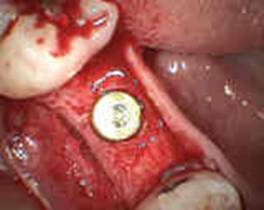

④Nobel Replaceインプラントを埋入します。

2回法で行うためカバースクリューで蓋をして、

粘膜下に置き縫合し、2ヶ月待ちます。